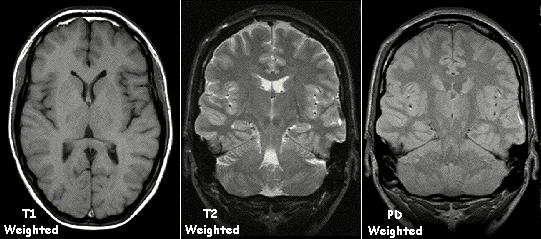

Here are some MRI images:

MRI images provide multiple "views" of the anatomy; these are usually the "T1-weighted", "T2-weighted", and "PD-weighted" views, which we'll discuss more in later lectures.

The combination of views, of course, provides more information that a single view. A tissue classification at a pixel can often be made by looking at the three different values of the corresponding pixel in the three views.